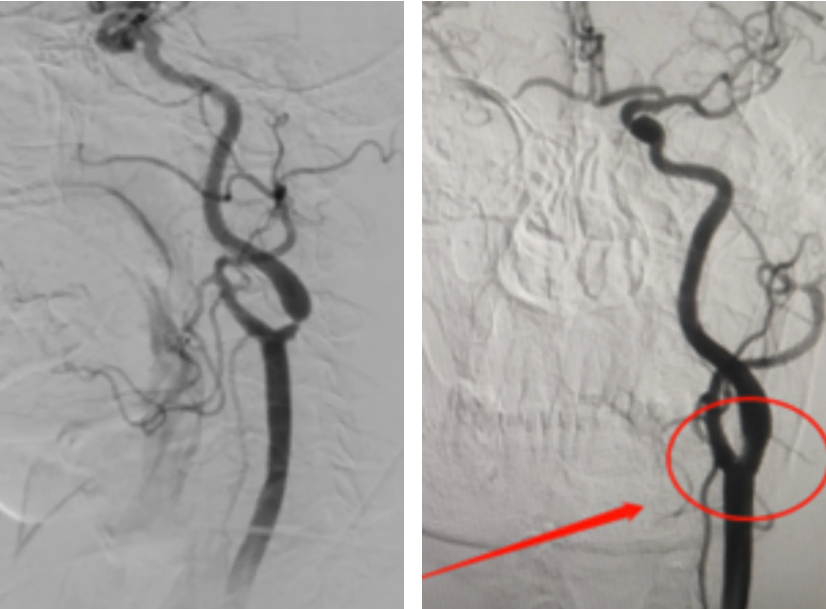

为彻底根治患者反复头昏的病情,科室展开了术前病例讨论,最终制定了适合的手术方案。在取得患者及其家属的同意后,择期施行了「颈内动脉支架植入术」。手术非常顺利,术后复查头颈部 CTA 提示,经左侧颈内动脉手术治疗后血管畅通,狭窄处充盈,患者自诉头昏基本恢复,头脑清醒,并顺利出院。

☑全脑血管造影术(DSA)

可以最准确地显示颈动脉的狭窄程度、斑块的形态和位置,以及侧支循环的情况。它是有创检查,需要住院在导管室局麻下进行。

▷颈动脉支架成形术 (carotid artery stenting,CAS) 是在患者的股动脉做一个 2 mm 穿刺小孔,将保护装置透过导管送至颈部动脉,再置放支架,即可将已呈现硬化、狭窄的颈动脉部位撑开,恢复脑组织供血。其特点为微创性、手术成效高且施行简易。